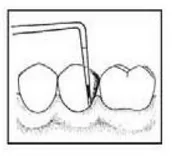

Instrumentem przedstawionym na ilustracji stosowanym w chirurgii stomatologicznej jest